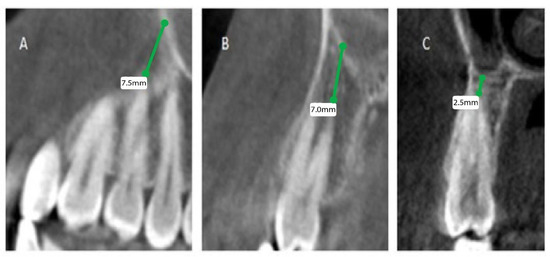

The patients’ files were assessed by the Department of Oral & Maxillofacial Surgery and Diagnostic Sciences, College of Dentistry, Prince Sattam Bin Abdulaziz University, Al-Kharj, Saudi Arabia, to record the gender and the age of the subjects included in the study from September 2020 to December 2020, and further divided as male and female patients, depending on gender and age, into 4 groups (0 to 20, 21 to 40, 41 to 60, and above 60). Mean distances between posterior maxillary roots (PMRs) from different teeth and the maxillary sinus floor (MSF) were measured using a software-calibrated tool. Each measurement was obtained by measuring a line drawn from the MSF to the nearest point of the apex of the root in two views, sagittal and coronal, and the mean distance was calculated (Figure 1, Figure 2 and Figure 3). The distance for each root and each tooth were recorded and transferred to the Excel sheet.

Figure 1.

CBCT sagittal view showing the distance between the maxillary sinus and the root of permanent maxillary (right). (A) First premolar buccal root, (B) first premolar palatal root, (C) second premolar root.

Figure 2.

CBCT sagittal view showing the distance between the maxillary sinus and the root of permanent maxillary (left). (A) First premolar buccal root, (B) first premolar palatal root, (C) second premolar root.